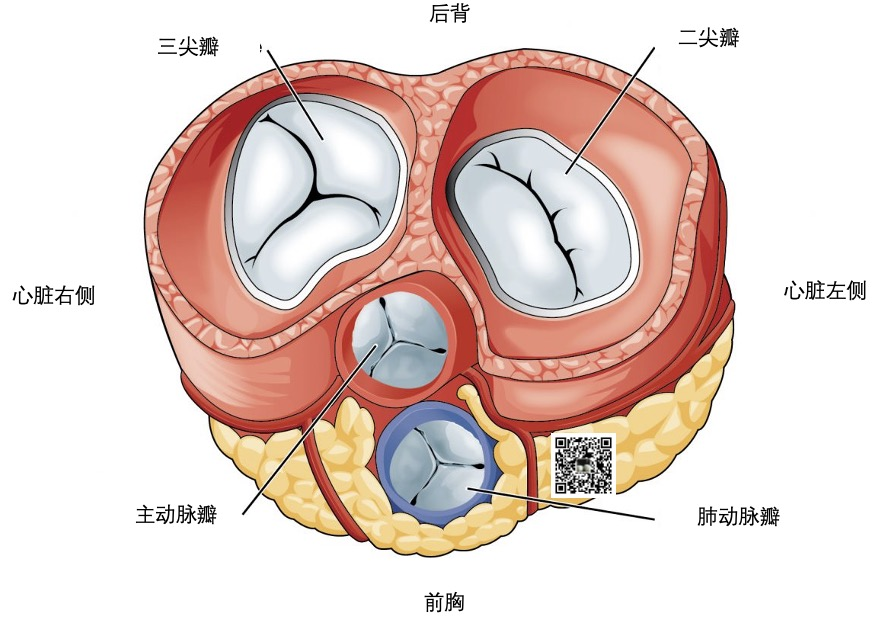

为了让血液流入或流出 4 个心腔,

心脏有 4 个瓣膜:

三尖瓣(tricuspid valve):三尖瓣允许缺氧的血液从右心房流向右心室。 -

肺动脉瓣(pulmonary valve):肺动脉瓣将血液从右心室泵入肺部,使血液获得氧气。 -

二尖瓣(mitral valve):二尖瓣使富含氧气的血液从左心房流向左心室。 -

主动脉瓣(mitral valve):主动脉瓣将富含氧气的血液从左心室泵向全身。